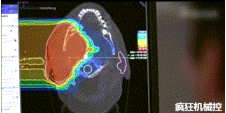

光柵掃描被集成到360°重離子治療一體機中,這種極其精確的照射方法以毫米為單位掃描腫瘤,可以保護健康組織且只治療腫瘤區(qū)域。

特別是腫瘤在高度輻射敏感位置或者諸如視神經(jīng)附近的復雜位置,可以通過選擇最佳射束入射角來減小這些器官的損傷。